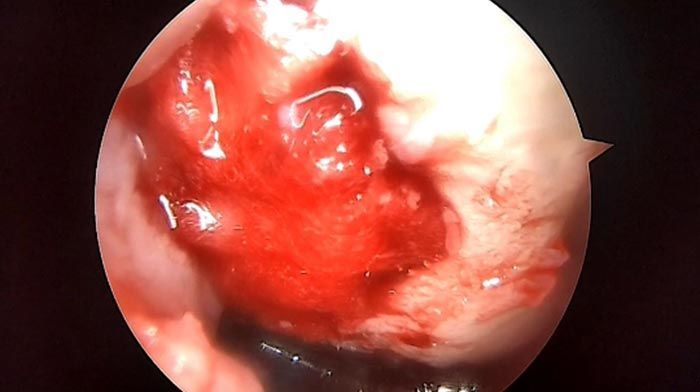

fracturas complejas, lesiones deportivas, cirugía de meniscos, de ligamento cruzado anterior, de ligamento cruzado posterior, cirugía de preservación del cartílago articular y reemplazos totales de las articulaciones hombro, cadera y rodilla.

cirugía de mínima invasión

ARTROUPN - Artroscopía de hombro

ButtonARTROUPN - Preservación de cartilago

ButtonARTROUPN - Cirugías de mínima invasión